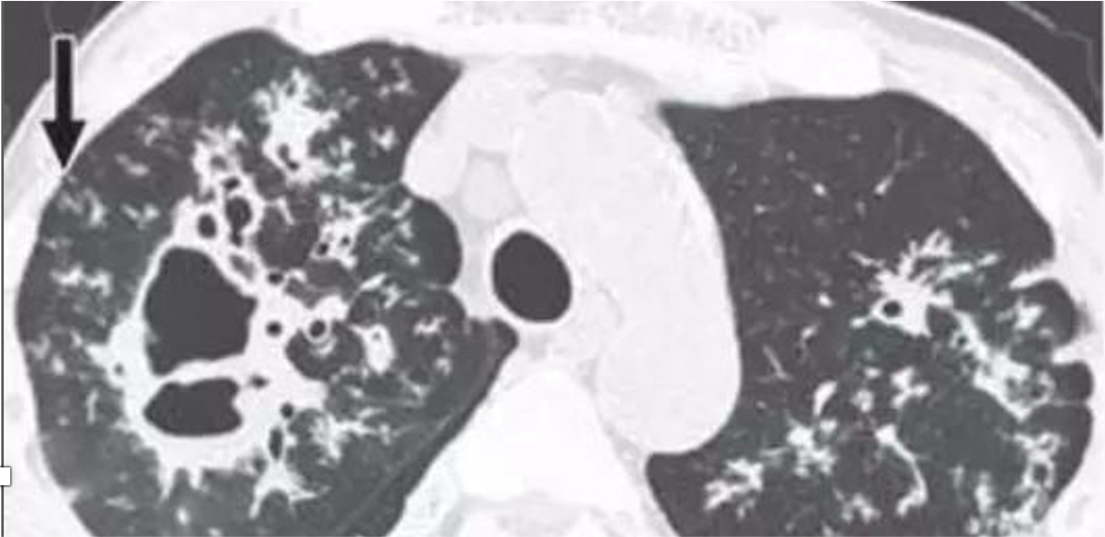

• Miliary TB refers to widespread dissemination of TB by hematogenous spread.

• Seen more frequently in reactivation TB.

The characteristic radiographic and high-resolution CT findings consist of innumerable, 1- to 3-mm diameter nodules randomly distributed throughout both lungs